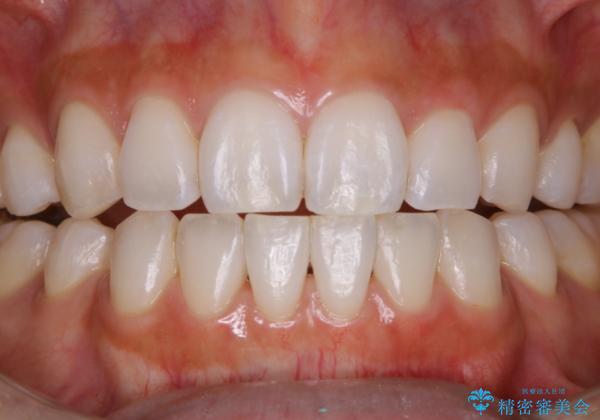

- フロスが以前よりも通りずらくなり、クリーニングしてほしいとのことでした。歯科医院でのクリーニングは3年ぶりとのことです。PMTC60分コースを行いました。

歯科医院で行なわれる専門家による徹底した歯面清掃をPMTC(Professional Mechanical Tooth Cleaning)といいます。専用の機器とフッ化物入り研磨剤を使用して、歯みがきで落とせない歯石や磨き残したプラークを中心に総ての歯面の清掃と研磨を行ない、齲蝕や歯周病になりにくい環境を整えます。

また、定期的に歯科医院にてクリーニングやチェックをしていると口腔内の変化があった場合の、早期発見につながります。口腔内の状態により、個人差はありますが約3か月を目安にPMTCを行うことがおすすめです。